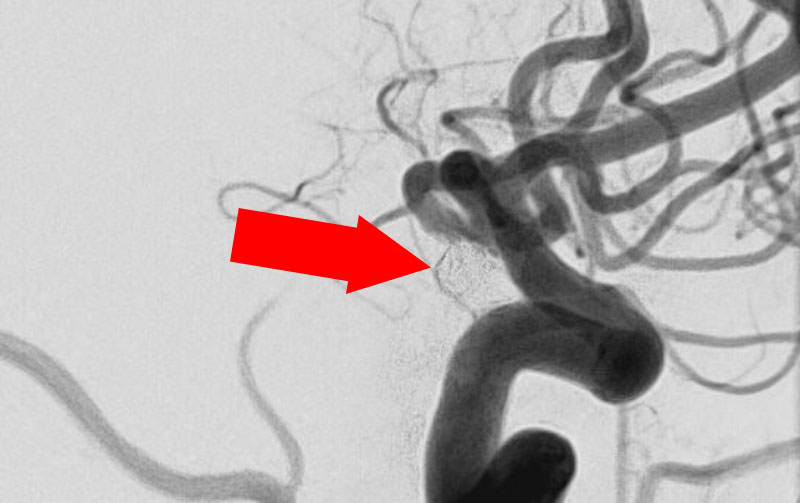

脳動脈瘤(血管内治療)実績一覧 (合計 791 件)

※ 画像をクリックすると拡大表示します。症例No.をクリックすると詳細ページを表示します。